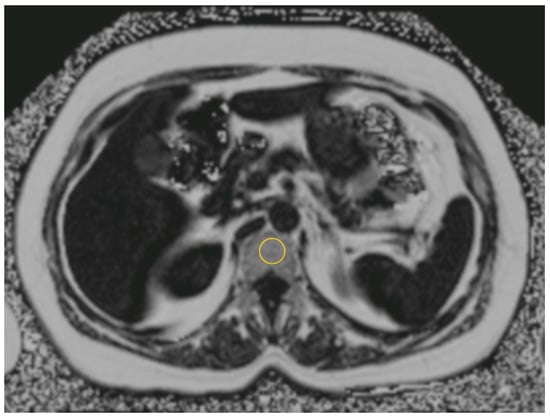

2.3. Imaging